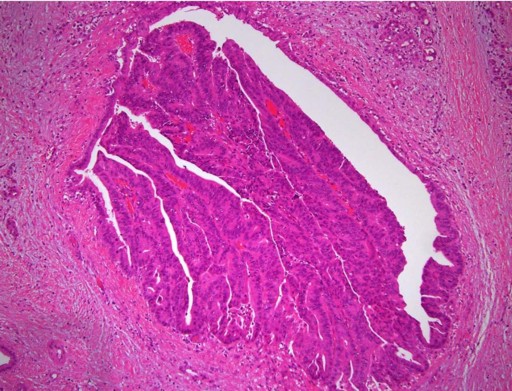

On August 2000, a 58-year-old female presented with large bowel obstruction, secondary to a malignant growth in the descending colon. She underwent an emergency left hemicolectomy and made an uneventful recovery. Histology showed moderately differentiated adenocarcinoma involving the serosal fat. The resected margins were free of tumor; however, 3 of the 18 regional lymph nodes were positive. The pathological staging was T3 N1 M0 and she received adjuvant chemotherapy which involved 6 cycles of FOLFOX chemotherapy (5-flurouracil and folinic acid and oxaliplatin). She was monitored regularly with ultrasound of the abdomen, carcinoembryonic antigen levels biannually and colonoscopy yearly for 2 years. The ultrasound of the abdomen was normal, carcinoembryonic antigen levels ranged between 2.2 and 4.7 µg/L (reference range: 0-2.5 µg/L) and colonoscopy showed small polyps which were benign. In March 2009 there was a sharp rise in carcinoembryonic antigen levels to 25 µg/L associated with a vague backache. A CT scan of the abdomen revealed a mixed density mass lesion with soft tissue and cystic components, measuring 6.8x4.8 cm in the area of the tail of the pancreas with possible left perinephric fat infiltration (Figure 1). No other metastasis was detected. A CT-guided biopsy suggested the possibility of adenocarcinoma. In April 2009, she underwent an exploratory laparotomy which revealed that the tumor in the distal pancreas was infiltrating the perinephric fat, the posterior wall of the stomach and the great omentum. She underwent a distal pancreatectomy and excision of the involved segment of the stomach, omentum and perinephric fat (Figures 2 and 3). Histology was reported as moderately differentiated adenocarcinoma with infiltration into the perinephric fat and the resected segment of the stomach. The adenocarcinoma was metastatic tumor from the colon confirmed by its histological appearance and strong positivity to cytokeratin 20 (Figures 4 and 5). The margins of the resected pancreas and stomach were clear of the tumor. She made an uneventful recovery. She received palliative chemotherapy in the form of 5 cycles of 5-flurouracil, oxaliplatin and bevacizumab. In October 2009, she presented with a mass in the left hypochondrium which on CT of the abdomen was found to be recurrent disease. She was provided care for the terminally ill and she ultimately died in January 2010, nine months after the resection of the metastatic tumor.

Figure 4. Metastatic adenocarcinoma of the pancreas (H&E x20). |